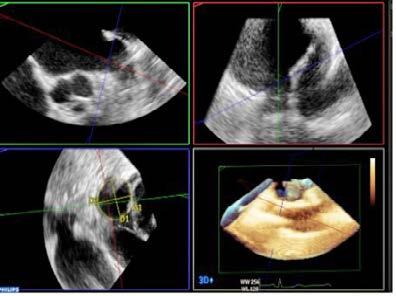

En octubre de 2024 se realizó, bajo anestesia general, cierre percutáneo de orejuela izquierda mediante acceso femoral derecho, guiado por angiografía y ecocardiografía transesofágica (ETE), y ajustando la dosis de heparina intraprocedimiento de manera estrecha (guiada por TTPA). Se implantó con éxito un dispositivo Amulet 25 mm sin complicaciones. Tras el procedimiento, se suspendió anticoagulación y valorando riesgo-beneficio, se inició antiagregación con clopidogrel, manteniendo control cardiológico y neurológico estrecho.

El paciente evolucionó favorablemente, permaneciendo estable y asintomático desde el punto de vista cardiovascular. Fue dado de alta a las 48 horas, tras confirmar adecuado posicionamiento del dispositivo en ETT. A los 45 días, el ETE de control evidenció el dispositivo de cierre de orejuela izquierda normoposicionado, sin evidenciarse flujos compatibles con leak peridispositivo mediante Doppler color. Se mantuvo el tratamiento con clopidogrel, sin registrar eventos hemorrágicos ni isquémicos posteriores.